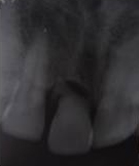

Pre Operation

Single Tooth Implant

Pre Operation X-ray

Placement of Bone Grafting